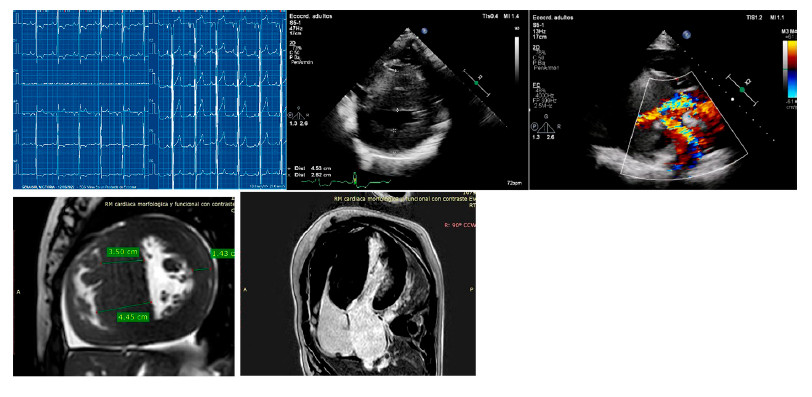

El caso índice es una mujer con hipertrofia severa diagnosticada a los 37 años, con implante de CDI por taquicardia ventricular (TV) monomorfa sostenida sincopal a los 47 años. La CRM que evidenció Miocardio no compacto (MNC) y G+ (MYH7: c.1208G>A (p. Arg403Gln). Sus 3 hijos presentan G+, dos de ellos con F+, ECG patológico (hipertrofia ventricular izquierda y ondas T negativas en la cara anterolateral) ECG y CRM de uno de sus hijos arriba y de la paciente abajo.